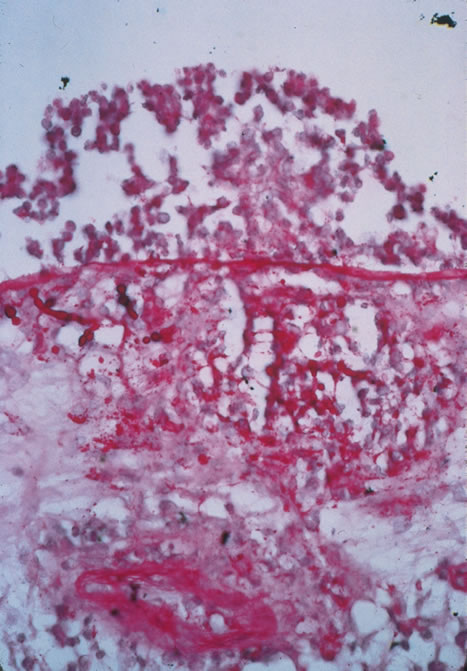

Any cell type may be infected, appearing larger than normal (cytomegalic) and demonstrating eosinophilic intranuclear “owl's eye” and smaller intracytoplasmic viral inclusion bodies, which are better seen with Giemsa or Papanicolaou's stains (Fig. 8). Histologic examination of tissue specimens, including bronchoalveolar lavage fluid and urine, may be useful for diagnosis.

Fig. 8. Typical lesion of cytomegalovirus (CMV) produces retinal necrosis with large cells possessing owl's eye inclusions.